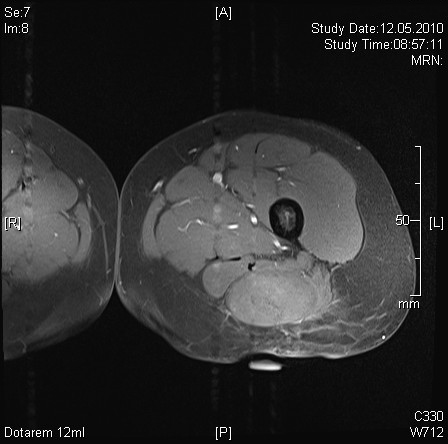

Weichteilsarkome sind bösartige Geschwulste, welche nicht wie Karzinome (Krebs) von Häuten oder Schleimhäuten ausgehen, sondern von den dazwischen liegenden Weichteilen, wie z.B. Muskeln, Bindegewebe oder Fettgewebe. Am häufigsten sind sie in den Extremitäten z.B. Oberschenkel (MRI eines Liposarkoms am Oberschenkel) oder im Fettgewebe hinter den Därmen (Retroperitoneum) lokalisiert (CT eines retroperitonealen Liposarkoms). Diese Geschwulste sind selten und bedürfen einer speziellen Behandlung, deren Hauptbestandteil die radikale, chirurgische Entfernung der Geschwulst ist. Die Behandlung ist interdisziplinär, wird also von verschiedenen Spezialistinnen und Spezialisten in Absprache durchgeführt und sollte an einem damit erfahrenen Spital erfolgen. In der Spital Thurgau haben wir in den letzten 10 Jahren durch ein hohes Aufkommen solcher Tumoren viel Erfahrung mit der Behandlung gewonnen (Statistik Weichteilsarkome am Kantonsspital Münsterlingen). Patientinnen und Patienten mit diesem Leiden werden durch unser Tumorboard beurteilt, die Behandlung festgelegt und anschliessend durchgeführt. Das Vorgehen wird eng mit dem Sarkomboard des Universitätsspitals Zürich abgestimmt und entspricht den Leitlinien des Swiss Sarcoma Advisory Boardes.

Die Operation ist der zentrale Teil einer kurativen (heilenden) Behandlung des Tumors. Bei der Operation wird der Tumor samt einem Mantel von gesundem Gewebe aus der Umgebung herausgelöst (Tumorausräumung retroperitoneal. Zustand nach der Tumorentfernung: der Patient ist 8 Jahre nach der OP tumorfrei und gesund). Alle Organe und Muskeln und Körperteile, welche mit dem Tumor in Berührung kommen, müssen ganz oder teilweise mitentfernt werden. Da dies zum Teil sehr grosse Tumoren sind und dadurch die Operationen auch sehr ausgedehnt sein können, erfordert diese Chirurgie eine grosse Erfahrung in diesem Gebiet (Wide-Excision am Oberschenkel. Die Patientin ist 6 Jahre nach der OP tumorfrei und gesund).